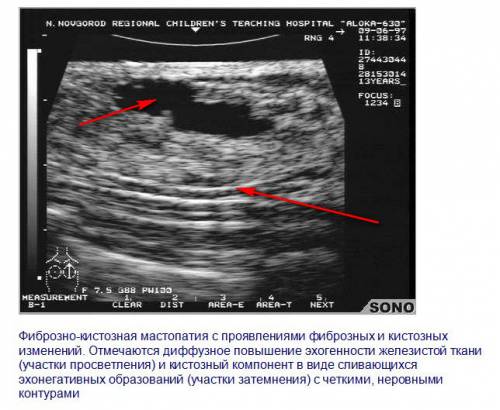

Фиброзно-кистозная мастопатия характеризуется как наличием полостей, заполненных жидкостью, так участками уплотнения. Образования имеют четкие границы.